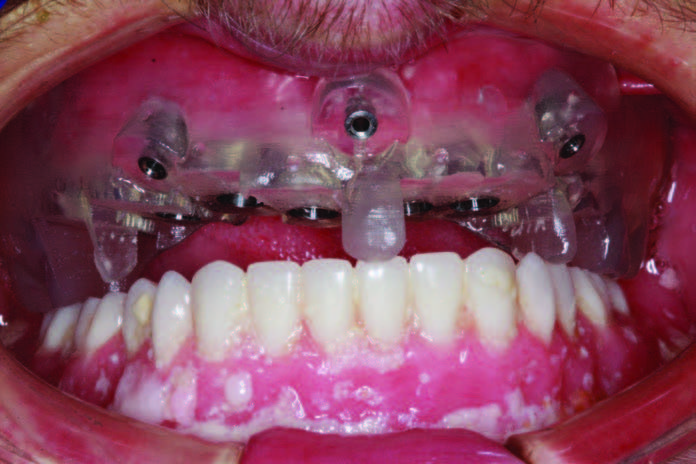

After implant placement and removal of the healing abutments, well-keratinized tissue was present that facilitated taking a good impression and cleanseability (Figure 12). After making the master impression, a baseplate and rim were ordered with instructions to engage every implant, leave windows for direct visualization at each implant site, and use metal componentry to aid as a secondary verification of seating (Figure 13). At this point, the Sheffield one-screw test was also performed to ensure the accuracy of the impression both with the baseplate and with the verification jig. When the custom abutments are designed and seated with abutment seating jigs, the verification jig is tried on; luted; and, if needed, separated and re-luted to ensure that there is no rocking or lifting with screw delivery (Figure 14). A custom tray was provided by the lab team, and it was tried in to learn the proper insertion path. Wax was then put in the screw access channel, and impression material (Aquasil Ultra Xtra) was injected around the abutments and used to load the tray. The impression was seated, and a finger was used to swipe away impression material to find the screw access channels. The working time of 5 minutes allows the dentist to relax while finding the screws. There is nothing more stressful than taking a full-arch implant impression and then losing your orientation and scrambling to seat it, as cutting off an impression intraorally can be a nightmare. This extended set and accurate impression material allows time for seating and the clearing of material (Figure 15). A full-arch impression is also made of the abutments after delivery to fine-tune gingival contours prior to fabrication of the monolithic BruxZir prosthesis (Glidewell Dental Laboratories).